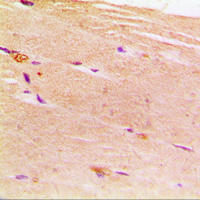

Immunohistochemical analysis of ACTN2 staining in human muscle formalin fixed paraffin embedded tissue section. The section was pre-treated using heat mediated antigen retrieval with sodium citrate buffer (pH 6.0). The section was then incubated with the antibody at room temperature and detected using an HRP conjugated compact polymer system. DAB was used as the chromogen. The section was then counterstained with haematoxylin and mounted with DPX. -